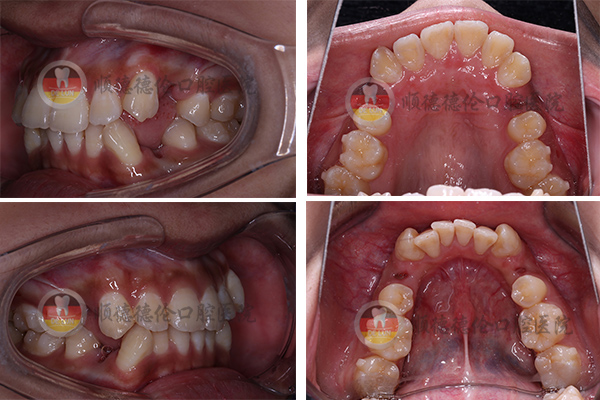

牙齒狀況:牙齒外突、擁擠、不整齊

3、拍口內照

4、取牙模